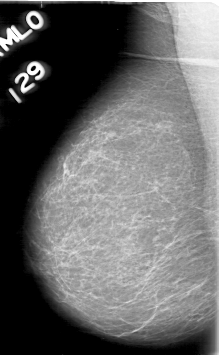

D_4055_1.RIGHT_MLO

RIGHT_MLO LINES 5311 PIXELS_PER_LINE 3271 BITS_PER_PIXEL 12 RESOLUTION 43.5 NON_OVERLAY